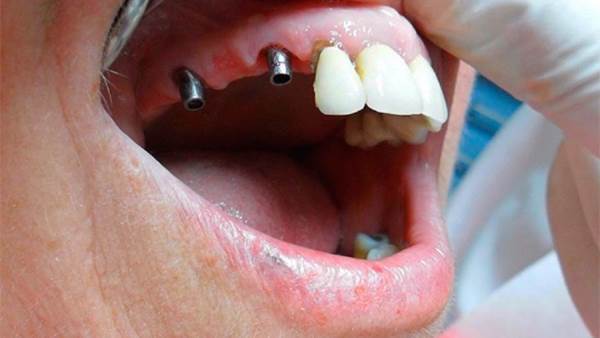

يترأس مراكزنا فريق مختار بعناية من خبراء زراعة الأسنان. وبعد عملية الزرع يتم تركيب التيجان والجسور ، والتي يتم تصميمها بأقصى قدر من الدقة والجمالية لمنحك الابتسامة المثالية.

يتم تخطيط وتنفيذ إجراء زراعة الأسنان بعناية لضمان أن ترميم الأسنان يبدو طبيعيًا في الشكل واللون والمكان. نعطي الأولوية لراحة مرضانا بالإضافة إلى الجماليات. وهذا يتطلب مزيجًا مثاليًا من العبقرية الفنية والجراحية. لذلك ، يتم تنفيذ جميع حالات الزرع لدينا من قبل فريق من أطباء الأسنان التجميليين وأخصائي زراعة الأسنان.